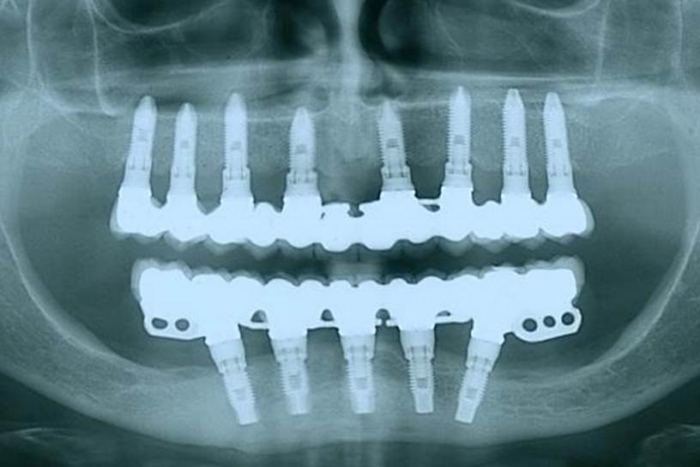

Raio X final

Raio X de 24 meses de controle